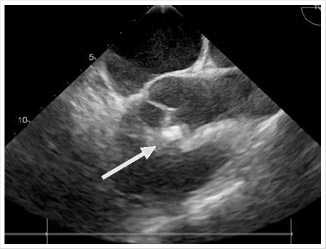

Рентгенография органов грудной клетки. Легкие расправлены, малый правосторонний гидроторакс. Сердце нормальной конфигурации. В проекции сердца определяется инородное тело металлической плотности (Рис. 1 А).

КТ-ангиография (Рис. 1 Б): КТ-картина ранения сердца – инородное тело (металлический предмет), частично в области межжелудочковой перегородки (МЖП) и частично интимно прилежит к структуре передней стенки восходящего отдела аорты; правосторонний гидропневмоторакс малого объема; сегментарные и субсегментарные ателектазы правого легкого; состояние после дренирования правой плевральной полости; линейная зона повреждения VIII сегмента правой доли печени, элевация правого купола диафрагмы.

Рис. 1. А – рентгенограмма органов грудной клетки, прямая проекция; Б – КТ-ангиограмма (режим MPR): инородное тело в проекции сердца.